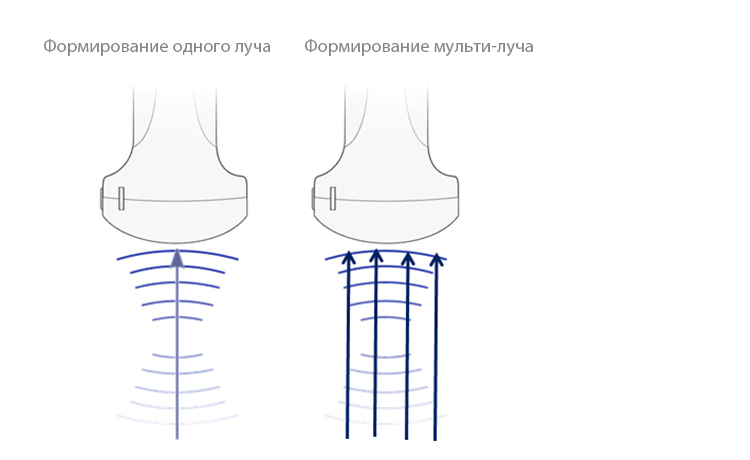

–§–æ—Ä–º–∏—Ä–æ–≤–∞–Ω–∏–µ –º—É–ª—å—Ç–∏-–ª—É—á–∞

–£–≤–µ–ª–∏—á–µ–Ω–∏–µ —Å–∫–æ—Ä–æ—Å—Ç–∏ –æ–±—Ä–∞–±–æ—Ç–∫–∏ —Å–∏–≥–Ω–∞–ª–∞ –æ—Ç –æ–¥–Ω–æ–≥–æ –ª—É—á–∞ –¥–æ 4 —Ä–∞–∑, —á—Ç–æ –ø–æ–∑–≤–æ–ª—è–µ—Ç –¥–æ—Å—Ç–∏–≥–∞—Ç—å –ø—Ä–µ–≤–æ—Å—Ö–æ–¥–Ω–æ–≥–æ –≤—Ä–µ–º–µ–Ω–Ω–æ–≥–æ —Ä–∞–∑—Ä–µ—à–µ–Ω–∏—è –∏ –±–æ–ª–µ–µ –≤—ã—Å–æ–∫–æ–π —á–∞—Å—Ç–æ—Ç—ã –∫–∞–¥—Ä–æ–≤.